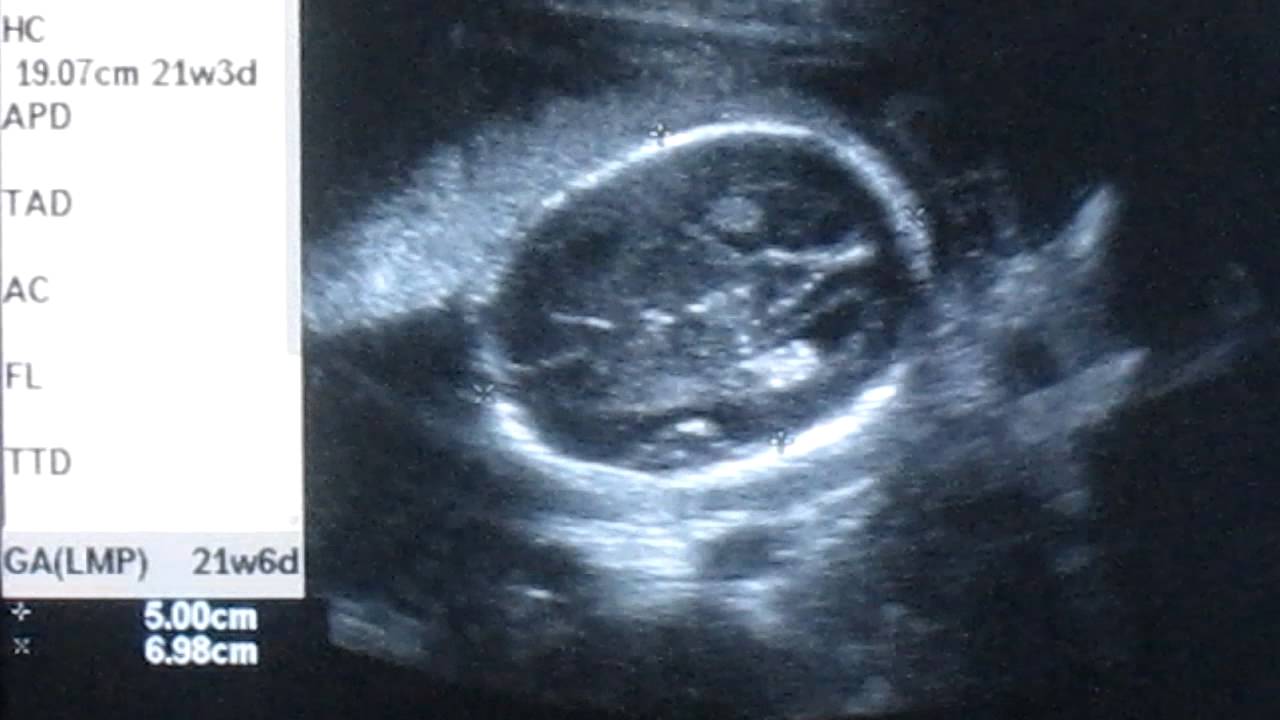

Беременность 22 недели мальчик

Беременность 22 недели мальчик 115 фото